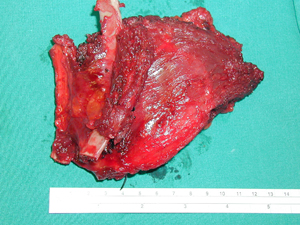

Εικόνα 3

Φωτογραφία χειρουργικού παρασκευάσματος. Ο όγκος του θωρακικού τοιχώματος που αφαιρέθηκε και η ιστολογική του εξέταση έδειξε ότι πρόκειται για δεσμοειδή όγκο.